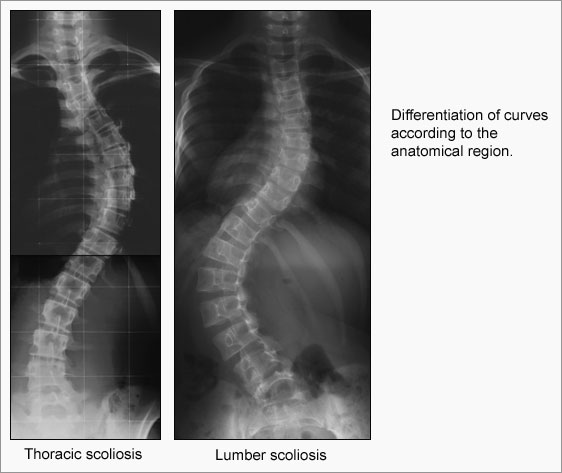

I know a little bit about scoliosis from my social worker days, when I has lots of clients who had it, usually people who also had some other problem, like CP. Anyway, the hunchback, fetal skeleton has kyphosis, something we are told that the Richard skeleton expressly did not have.

Second, the Richard skeleton, the way it is laid out, as an anthropological specimen, just doesn't look like anything in nature. No one with scoliosis has a spine that juts out, then becomes straight again, although from pictures I've seen, some people who have had fractured vertebrae, and been lucky enough not to get spinal cord damage, sometime get a funny kink in the spine, that looks like scoliosis at first glance, but isn't. The jut in that skeleton is way too pronounced to be the result of that, either, though.

Anyway, when someone has a wide angle c-curve running the length of the spine, it's one thing, but when someone has an acute angle curve, invariably, the spine then curves also to the other side, so the upper body weight is still evenly distributed, and you get an s-curve. It's also pretty unusual for the curve to end below the neck, so the cervical vertebrae are all straight.

The images you post look pretty similar to what was shown on the programme. The curvature was significant and lateral apparently. The programme is well worth watching when you do get the chance.

Wow. That first pic is from someone who had a combination of scoliosis, and kyphosis, giving him a corkscrew spine. That must have been awful. If you look at the ribcage, it looks like the lungs couldn't expand very well. At least it looks like a male pelvis. I'll bet a women with that kind of curvature was doomed to mid-term miscarriages. I'll bet that person was in a wheelchair toward the end of life.

The lower ones are s-curves. My point about the curve being only one direction is that people with scoliosis tend to carry themselves so their head is still more or less over their coccyx. A very obtuse curve the length of the spine tends to allow for this, but an acute curve, or even one that is more than 90 degrees, but not much more, usually causes a compensatory curve the other direction, and so you get the s-curve.

Richard was traditionally referred to as "Richard Crookback" or "Crookback Dick" and it strikes me that the shape of the vertebrae/spaine as displayed would make that a VERY reasonable - even literal description.